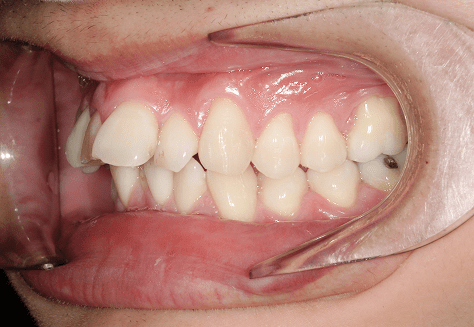

M.H

治療前

治療後

主訴

前歯が出ている。下の歯並びが特に気になる。奥歯でしっかり噛めない。

診断

上顎前突・叢生・シザーズバイト

年齢/性別

20代/男性

抜歯部位

下顎両側大三大臼歯(口腔外科にて)

上顎両側第一小臼歯・下顎左側側切歯

(当院にて5,500円×3) -

使用装置

上下エッジワイズ→インビザライン(PBM使用)

保定装置

上下ビベラリテーナー

基本料金

880,000円

5,500円×44回

治療期間

3年6カ月